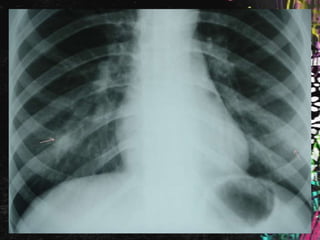

Diagnóstico: Masa       mediastínica a

estudio.

Rx de tórax en planta:

Se comenta el caso al Radiólogo, quien informa

que se trata de una falsa imagen

provocada por pelo largo recogido en moño

o coleta, por lo que es dada de alta con

seguimiento en consulta externa de Medicina

Interna con Rx de Tórax y analíticas; por la

presencia de imagen de vidrio deslustrado en

el TAC poco valorable por la escasa

inspiración de la paciente.

Rx de tóraxen planta:

Se comenta elcaso al Radiólogo, quien informa que se trata de una falsa imagen provocada por pelo largo recogido en moño o coleta, por lo que es dada de alta con seguimiento en consulta externa de Medicina Interna con Rx de Tórax y analíticas; por la presencia de imagen de vidrio deslustrado en el TAC poco valorable por la escasa inspiración de la paciente.